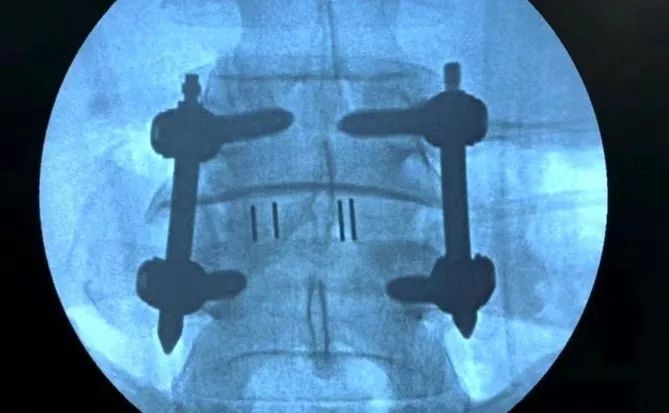

代表新桥医院参赛的骨科专家张超副教授介绍,腰椎间盘疾病是60岁以上人群的常见疾病,由于现代生活方式改变在年轻人中也高发,常因腰腿疼痛严重影响患者生活质量。微创脊柱外科技术目前已成为治疗腰椎间盘疾病的有效手段,具有创伤小、恢复快等特点。但既往微创技术适应症单一,手术器械多依赖进口,不符合中国人体型特点,操作难度大且医疗成本高。

新桥医院微创脊柱外科团队在周跃教授带领下,秉承精准化、微创化、个体化理念,提出了“靶点技术”理论,并通过近10年不断的创新研究,创建了腰椎间盘退变性疾病微创外科治疗的技术体系,解决了术中神经减压、脊柱固定、椎间融合三大技术难题,并根据中国人体型和解剖特点,与医疗器械公司联合研发、生产“Z”系列产品。本项目将关键技术集成“3Z”腰椎治疗系统,在疗效好、创伤小、并发症少的同时,为患者人均节省30%的医疗费用。

我国首套自主研发微创脊柱固定Zina系统,临床应用200余家医院,并通过美国FDA认证,成功销往德国、法国等国家,实现产值1.4亿元。在实现技术绩效的同时,还肩负着社会责任,他们依托中国医师协会脊柱内镜医师培训学院,近年来每年连续举办微创脊柱外科继续教育培训100余期(每期两周),培训国内外医师1200余人次,举办相关国际、国内学术会议10余次推广交流该创新项目,帮带基层医院,并在西藏高原开展该项目,造福官兵和人民。